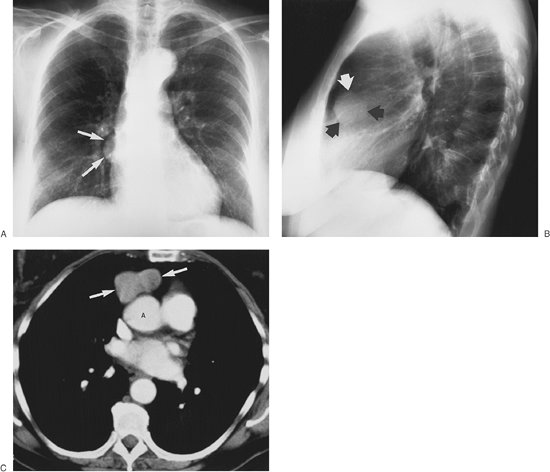

FIGURE 6-9. Benign thymoma. A: PA chest radiograph of a 70-year-old woman shows a rounded mass overlying the right heart border. The visualized margins are well circumscribed (arrows). B: Lateral chest radiograph suggests that the mass is located in the anterior mediastinum (arrows). C: CT scan shows a peanut-shaped mass of fairly homogeneous attenuation (arrows). The mass is located anterior to the ascending aorta (A), above the right ventricular outflow tract, a typical location for thymomas.